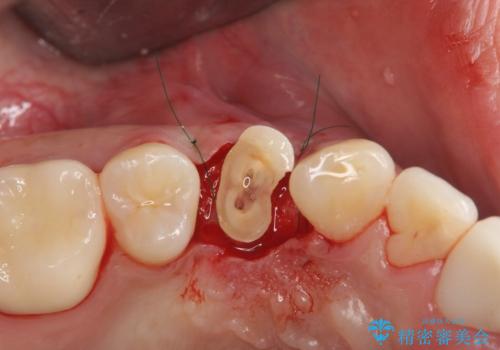

初診時の状態では虫歯が大きすぎて取り切ることができなかったため、まず歯を骨から引きあげて虫歯がしっかり除去できる状態にしました。

虫歯を取り切った後は、歯を引きあげたことで一緒に上がってきてしまった骨をならしていきます。